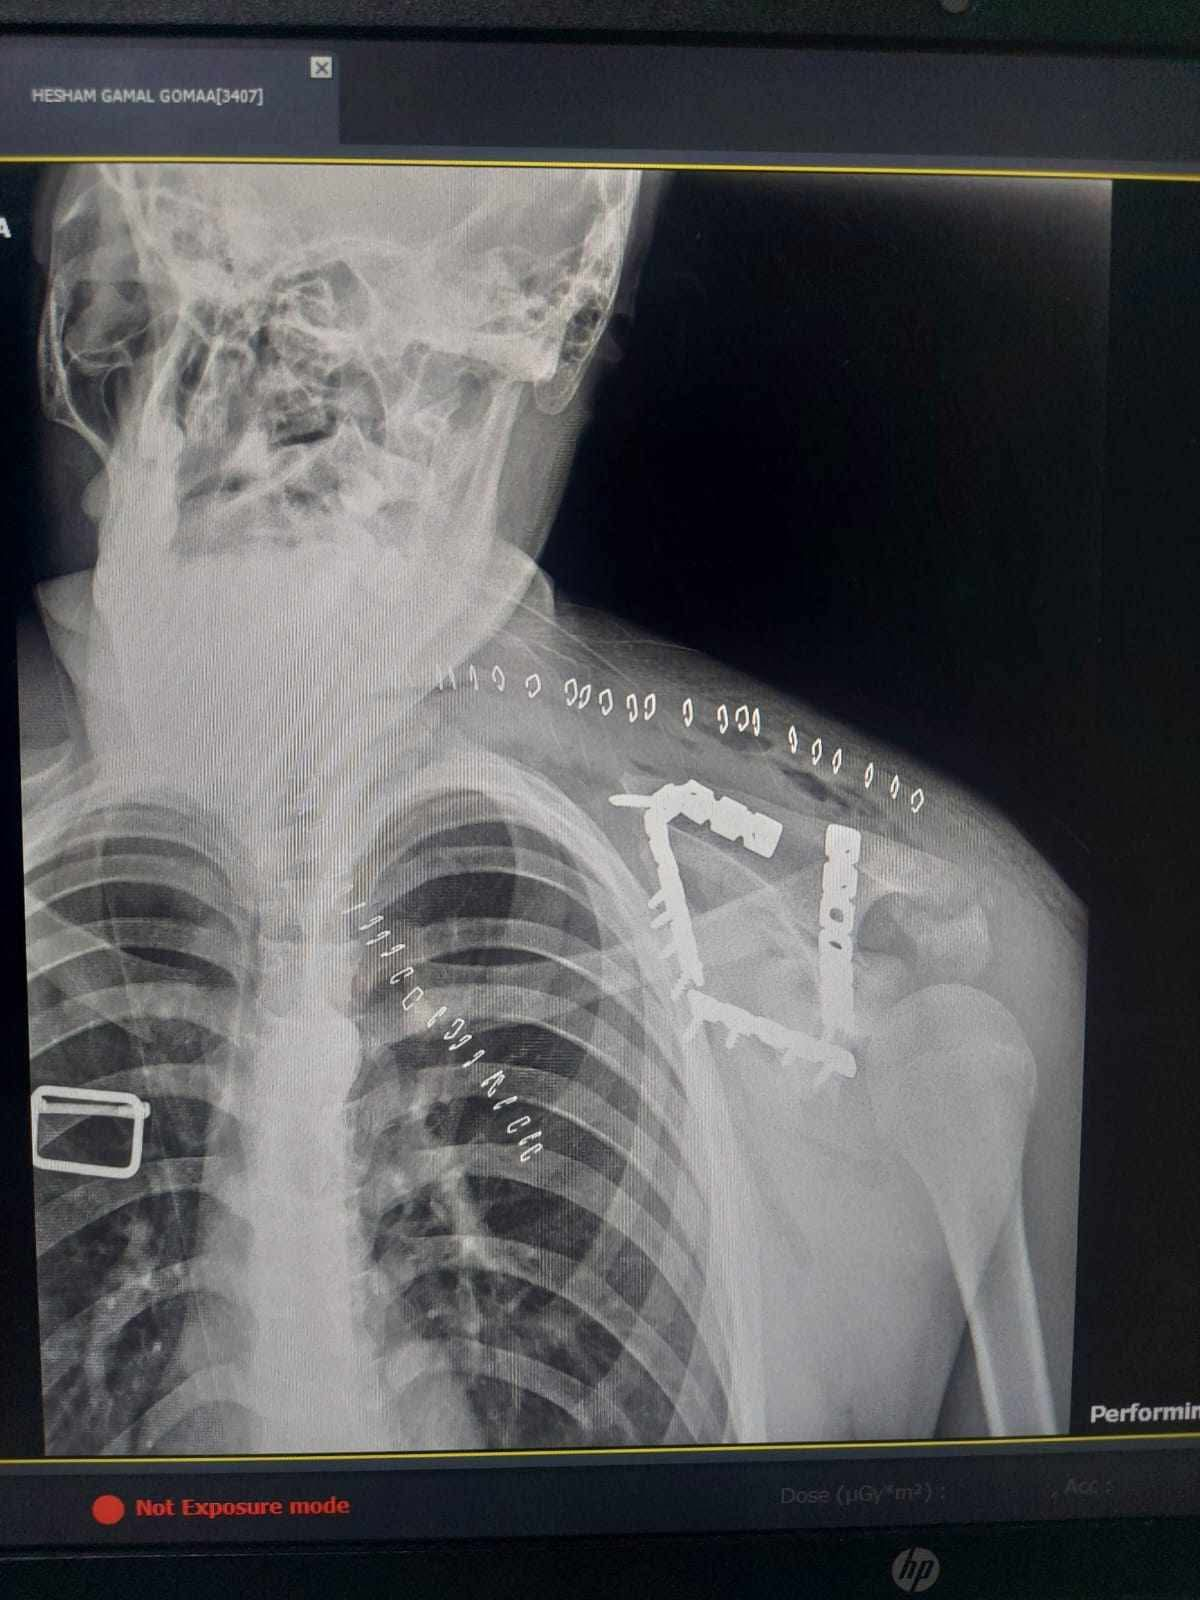

شهد مستشفى التأمين الصحي بالفيوم واقعة طبية متميزة بعد استقبال شاب يبلغ من العمر 17 عاما كان يعاني من كسر مفتت بعظمة لوح الكتف وهي من الاصابات الدقيقة والنادرة التي تحتاج الى تدخل جراحي متخصص نظرا لتعقيد موقعها وتشابكها مع العضلات والمفاصل المحيطة ما يجعل التعامل معها تحديا كبيرا امام الفرق الطبية.

خضع المريض لعملية جراحية معقدة استمرت نحو 4 ساعات تحت تأثير التخدير العام حيث قام الفريق الطبي برد وتثبيت الكسر باستخدام الشرائح والمسامير في اجراء دقيق يتطلب مهارة عالية وخبرة كبيرة خاصة في هذا النوع من الاصابات النادرة.

العملية مرت بنجاح دون حدوث مضاعفات وتمكن الاطباء من تثبيت العظمة بشكل سليم يساعد على استعادة المريض لوظائف الكتف تدريجيا خلال فترة العلاج.